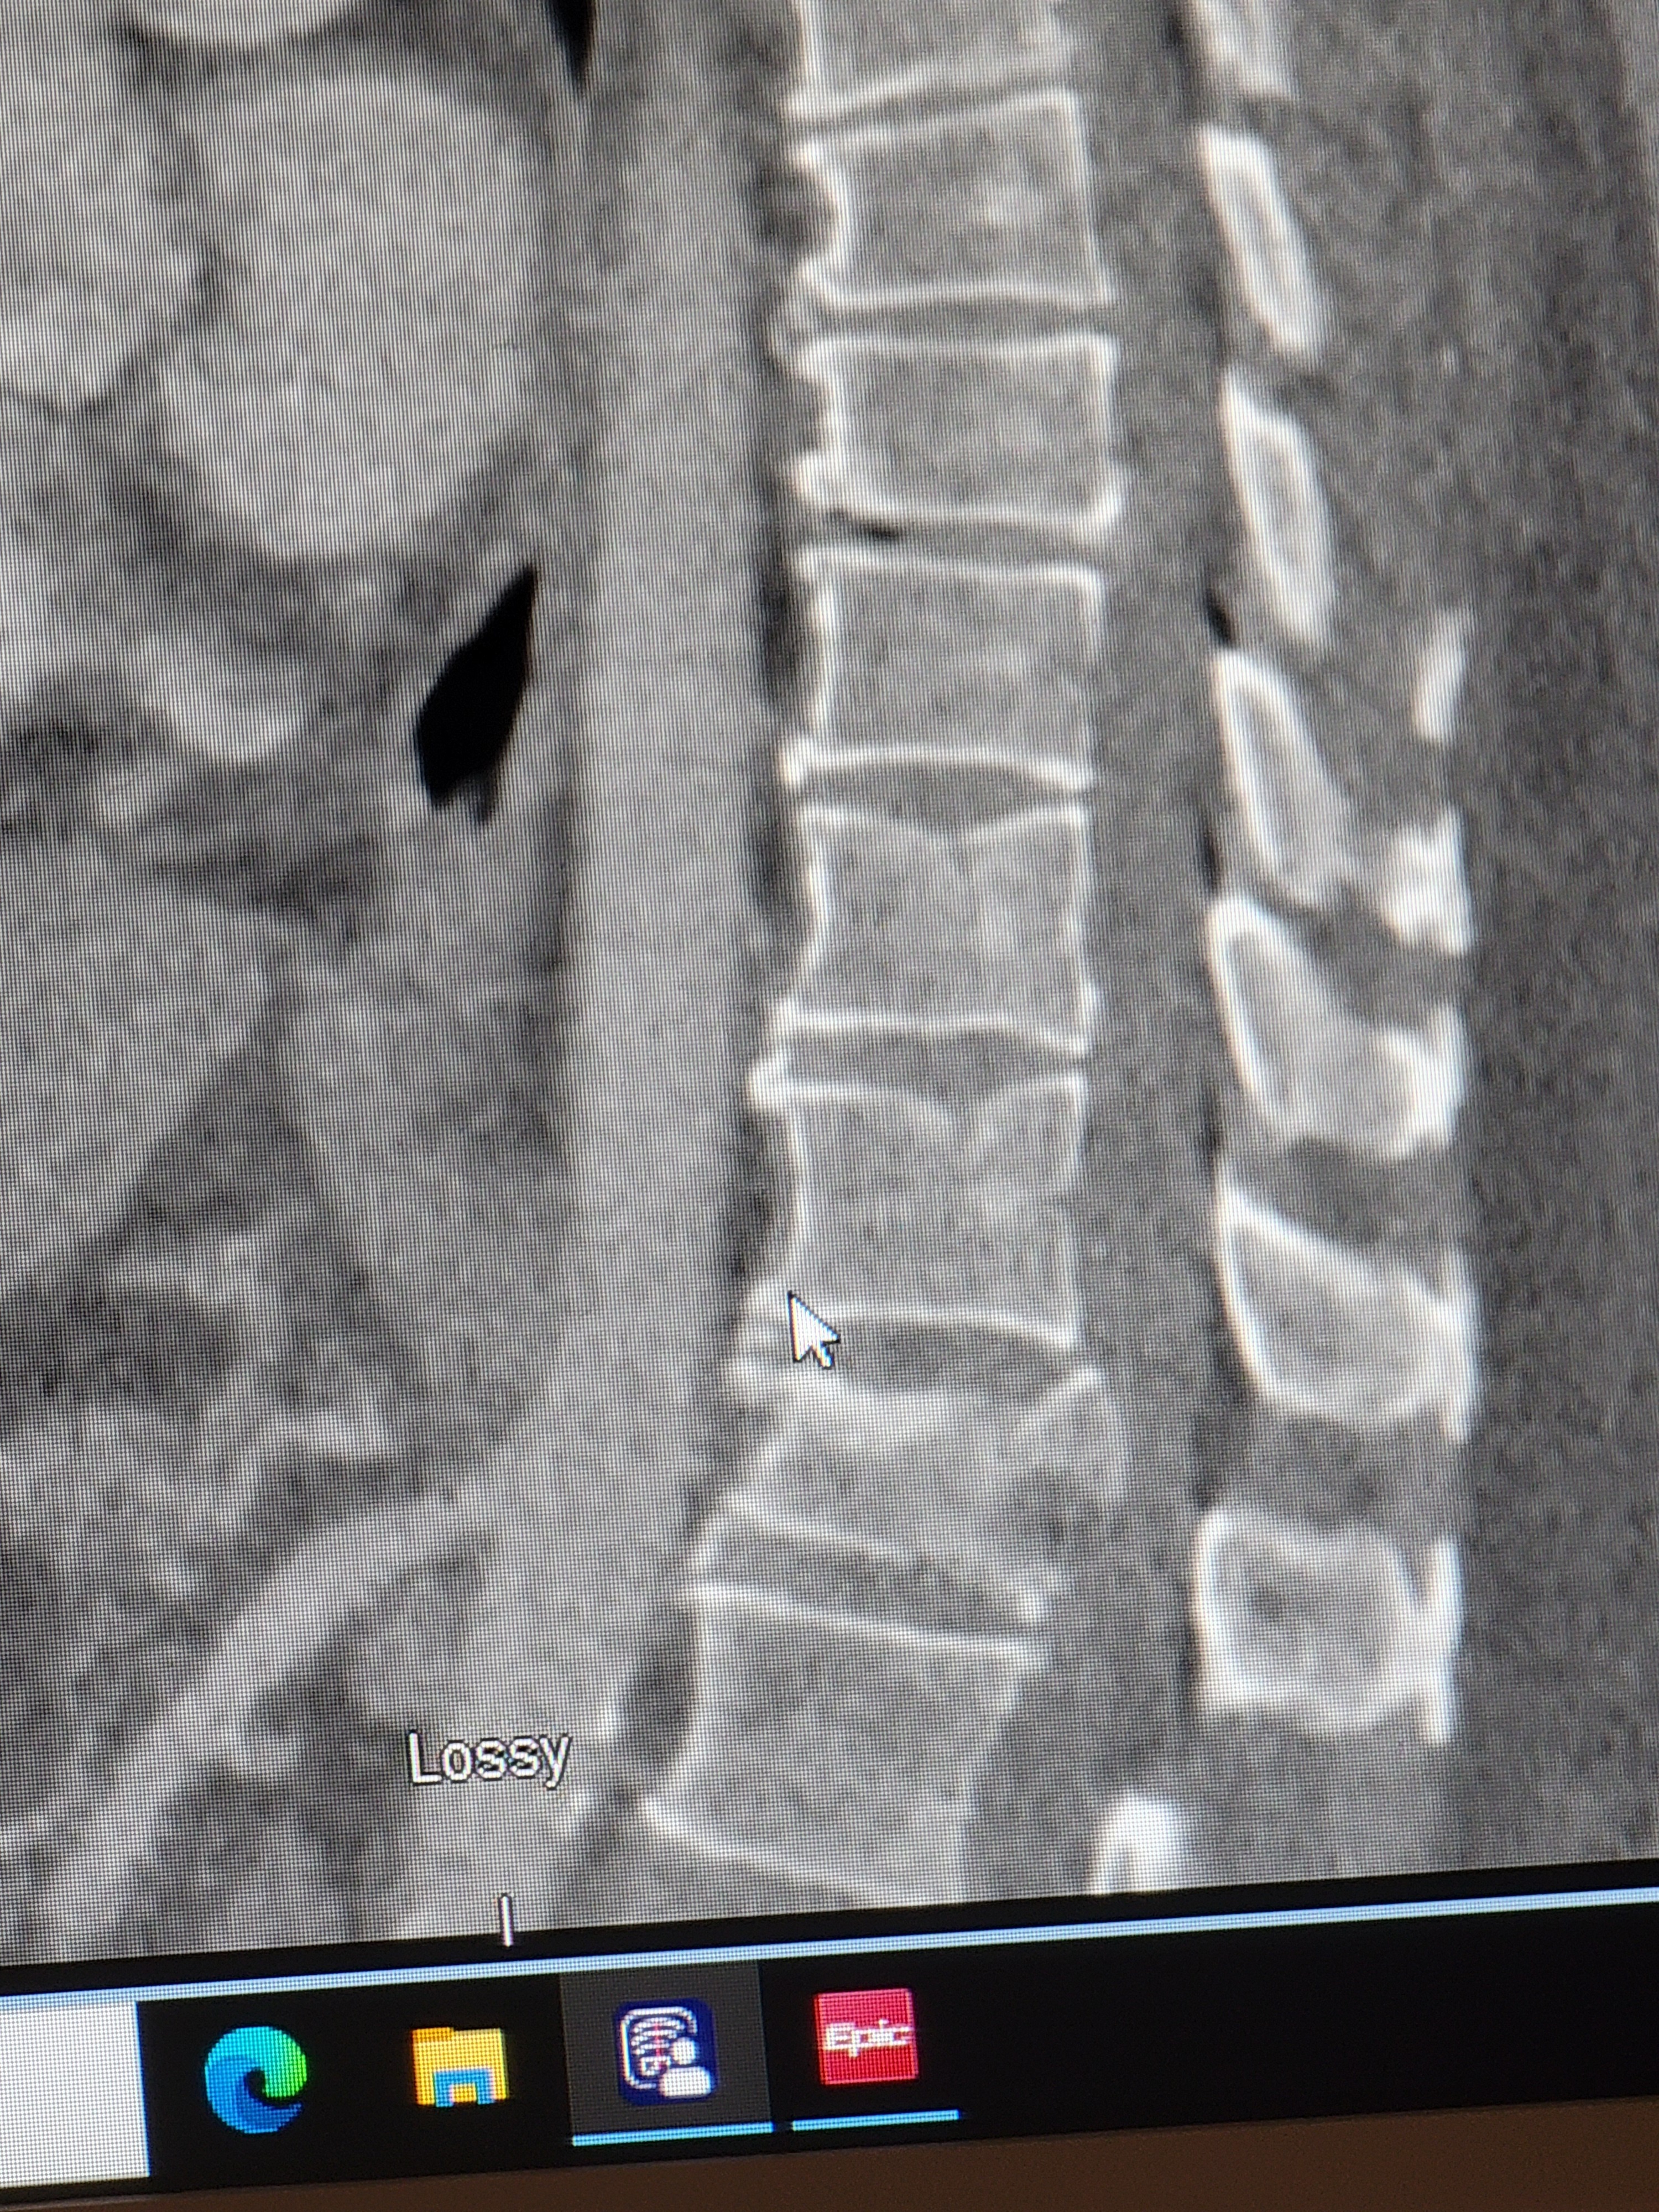

My husband was in a car accident Saturday on his way to work. Unfortunately, he broke a vertebra in his spine causing instability. He had to have emergency surgery to repair it and has a long road ahead for his recovery.